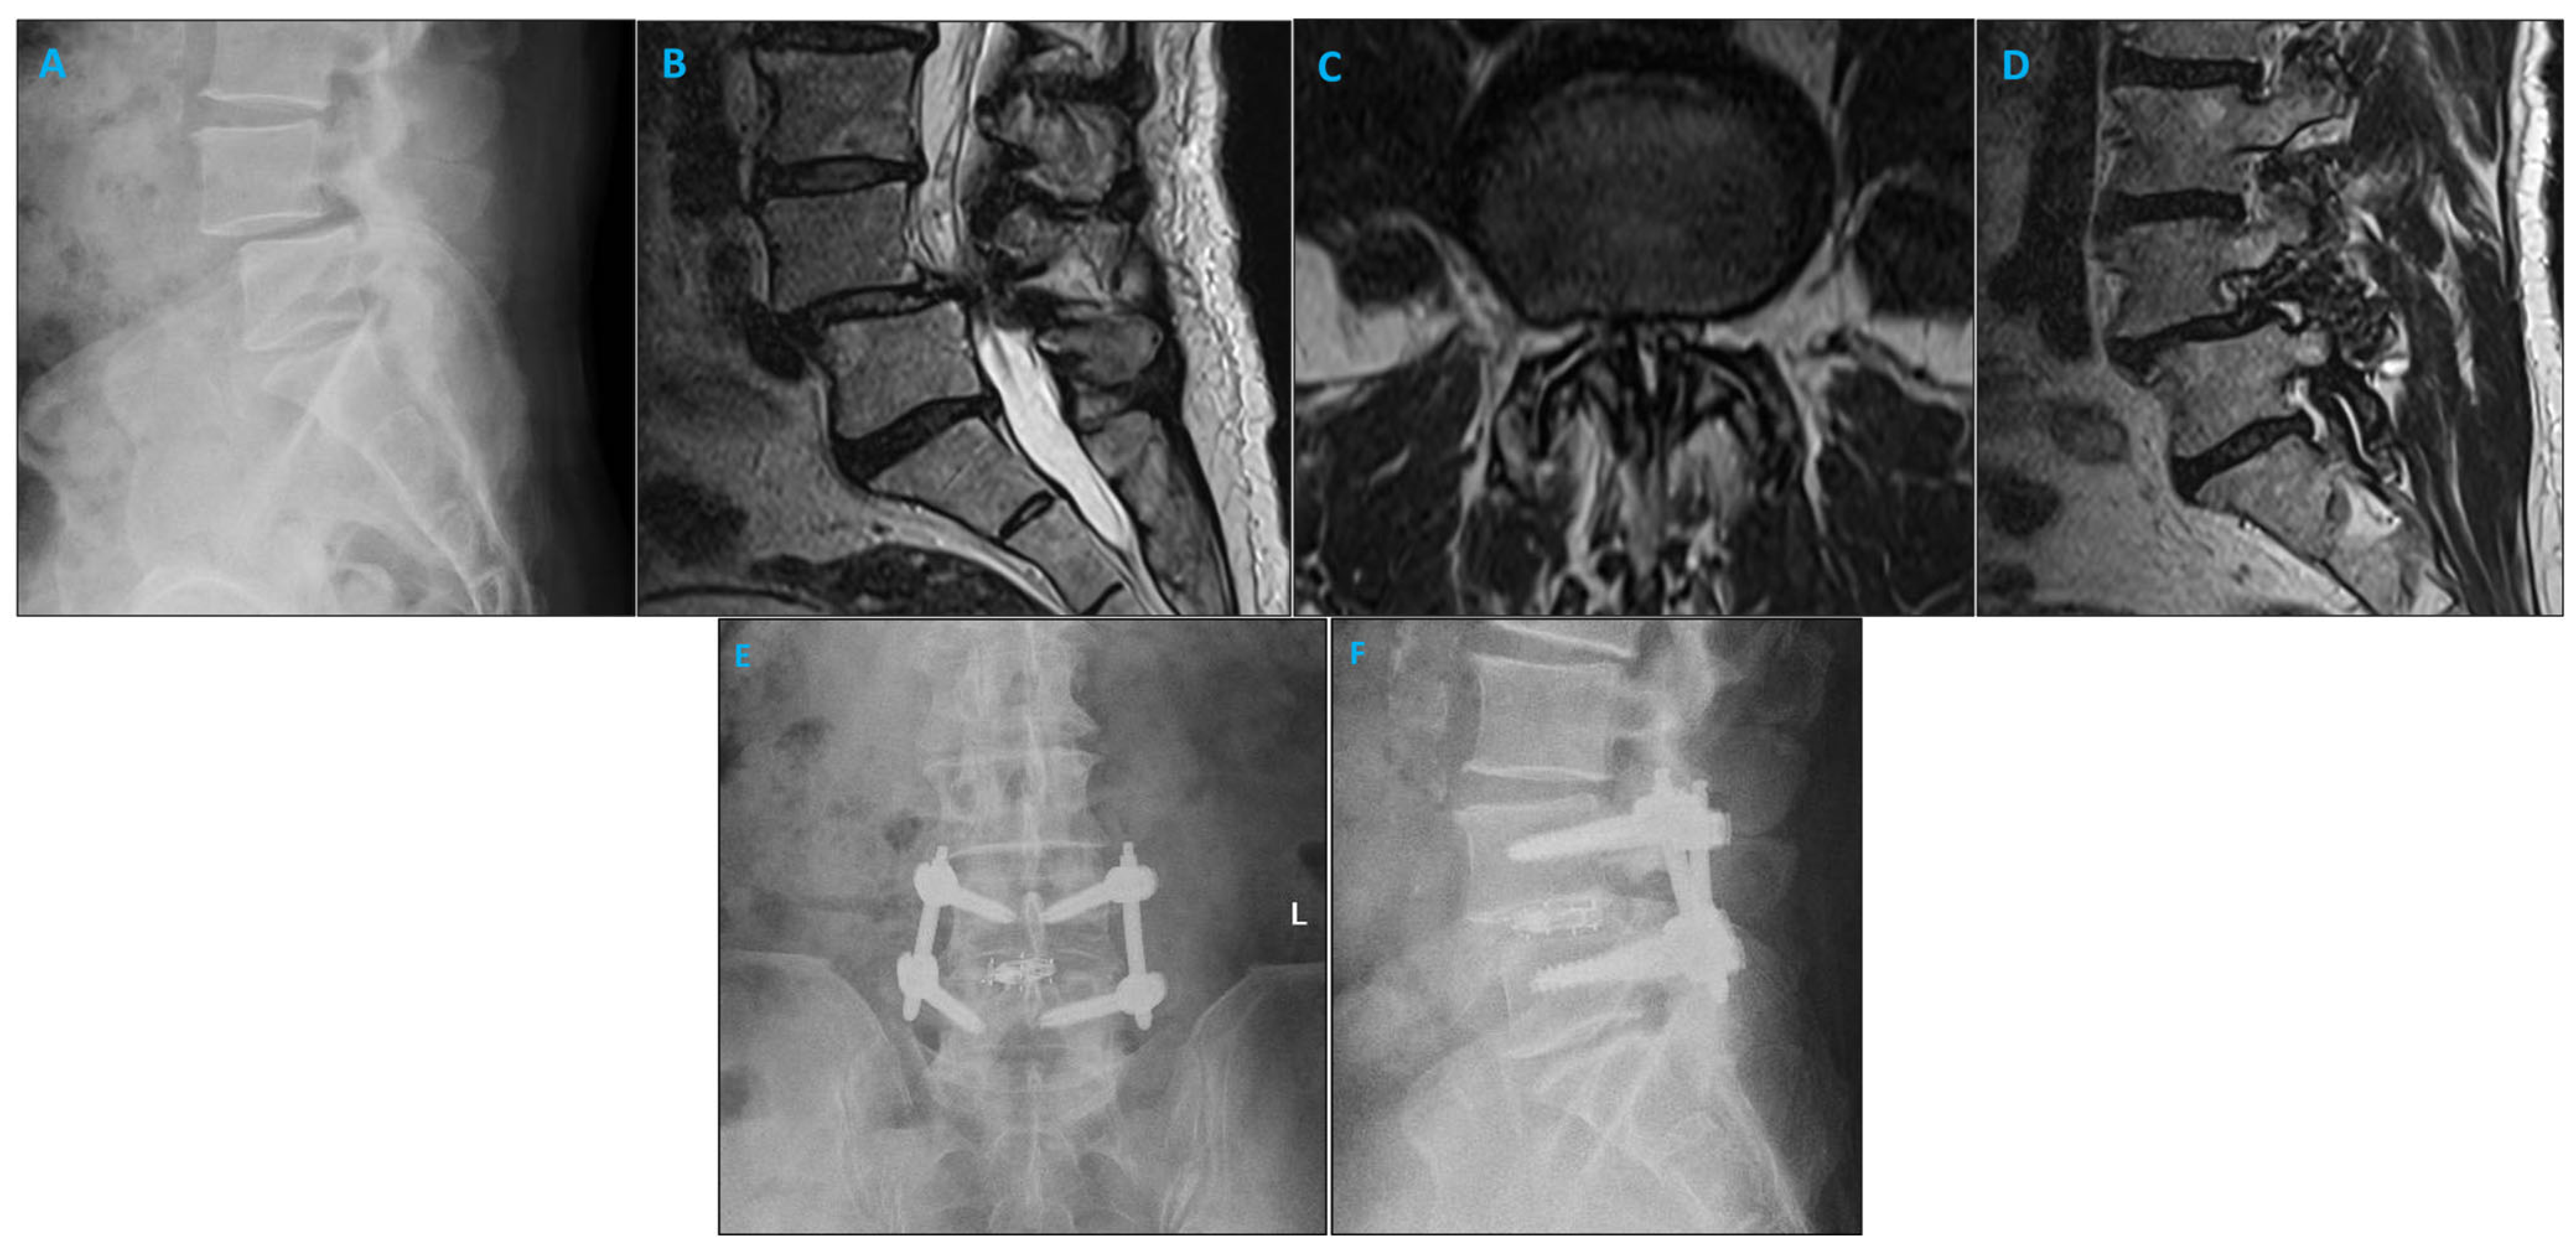

2.2. Surgical Approach

4. Discussion